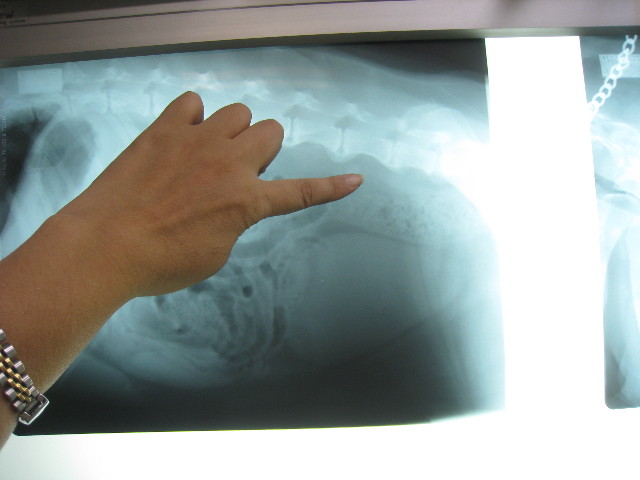

腰回りに通じるリンパが腫れていないかレントゲンを撮ってもらって検査。

指先辺り一帯が、腰回りに通じるリンパらしいけど、腫れたりの異常なし(^o^)v

ということで今のところ肛門嚢腺癌の転移や再発の徴候はなし(*゚Ω゚)/ウィッス!!

変形性脊椎症もけっこうひどくて下はいくつもブリッジになってるよね。

ブリッジになると神経には当たらないから直接の痛みは少ないけど、柔軟性がなくなって骨の動きが悪くなるからそれはそれで負担なんだって。

こちらは肺。

過去のフィラリアの影響などであいかわらず白っぽいけど、前回(7月2日)と変わっていないので大丈夫♪